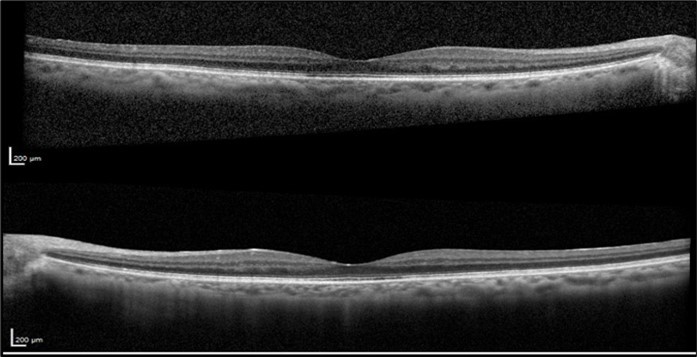

The patient was closely monitored every three months during the first year following the discontinuation of Leflunomide, and then every six months thereafter. Follow-up evaluations included repeated VA tests, fundus examinations, and SD-OCT imaging to assess the resolution of CME and any improvements in visual function. After two years of discontinuing Leflunomide, the CME resolved without recurrence and without the need for any topical treatment. At her final visit, VA was OD 20/25 and OS 20/25. OCT OU revealed resolution of the CME with a dry fovea (Figure 4).

Figure 4.Optical coherence tomography of both eyes revealing the sustained resolution of the cystoid macular edema after Leflunomide discontinuation.